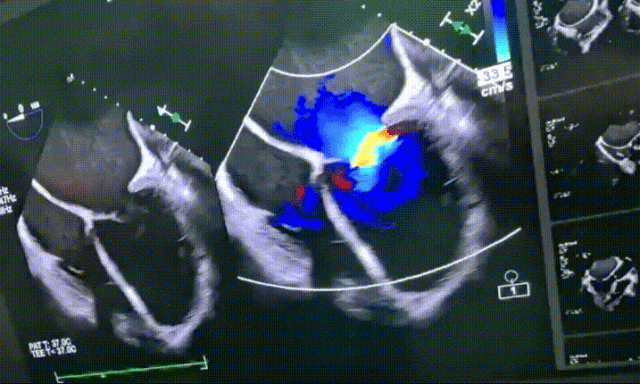

入室食道超声示:LV 65mm,无主动脉瓣反流,二尖瓣大量反流,三尖瓣少量反流,无心室内血栓,无卵圆孔分流,无室壁瘤。

入室食道超声